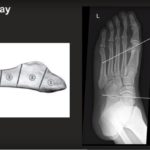

Jones Fracture

Courtesy: Prof Nabil Ebraheim, University of Toledo, Ohio, USA Metatarsal Fractures Metatarsal fractures can involve: First metatarsal Fifth metatarsal Second, third, and fourth metatarsals (including stress fractures) 1. First Metatarsal Fractures Key Points Different from fractures of the second, third, and fourth metatarsals. The first metatarsal carries a greater load. Malunion may cause: Transfer lesions […]